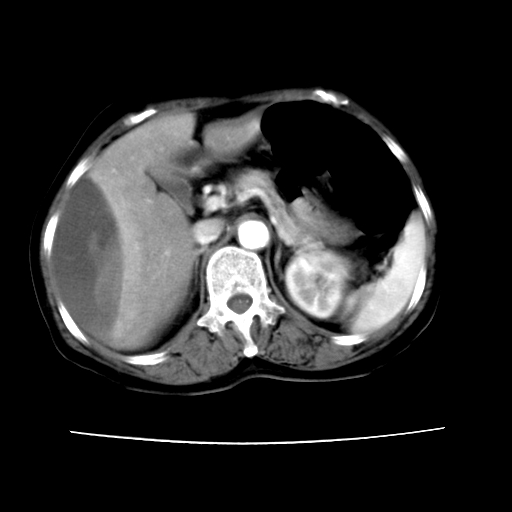

标题: CT16642:男62岁,突发性上腹部疼痛来诊。请讨论!

2008-6-10ct平扫

ct增强

6月份ct片显示肝内巨大混杂密度团块,伴包膜下积液(内含液液平面),增强多无明显强化。只能考虑肝占位病变,并肝内、血膜下血肿。肝ca并出血多见,而肝血管瘤并破裂出血少见。

6月份ct片显示肝内巨大混杂密度团块,伴包膜下积液(内含液液平面),增强多无明显强化。只能考虑肝占位病变,并肝内、包膜下血肿。肝ca并出血多见,而肝血管瘤并破裂出血少见。